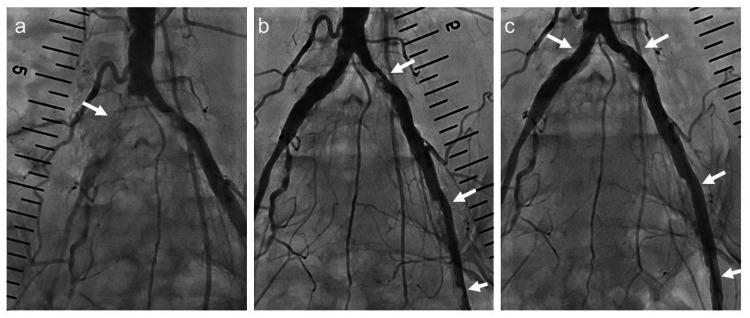

Percutaneous endovascular treatment of peripheral vascular disease with small-caliber short sheaths may lead to device removal difficulties. A 50-year-old woman on hemodialysis underwent endovascular intervention for right common femoral artery stenosis, via the right brachial artery. A 4-Fr short sheath was used for the procedure owing to a previous hematoma at the puncture site. However, the balloon catheter could not cross the calcified lesion and was difficult to remove. A microcatheter was inserted and withdrawn, but the guidewire was kinked and could not be retrieved. Surgical retrieval of the guidewire and balloon catheter was performed. The kinked guidewire and microcatheter had migrated outside the vessel. In peripheral vascular intervention, the use of a long sheath in the brachial artery approach is important. Forcible removal of a difficult-to-remove catheter may cause further vascular damage. Therefore, it is essential to stop immediately and consider surgical treatment.

使用小口径短鞘进行经皮血管腔内治疗周围血管疾病可能会导致器械取出困难。一名50岁接受血液透析的女性因右股总动脉狭窄,经右肱动脉进行血管腔内介入治疗。由于之前穿刺部位有血肿,该手术使用了4F短鞘。然而,球囊导管无法穿过钙化病变且难以取出。插入并撤出了微导管,但导丝出现扭结且无法取出。遂进行了手术取出导丝和球囊导管。扭结的导丝和微导管已迁移至血管外。在周围血管介入治疗中,在肱动脉入路中使用长鞘很重要。强行取出难以取出的导管可能会导致进一步的血管损伤。因此,必须立即停止操作并考虑手术治疗。